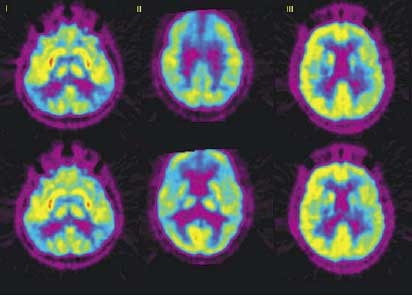

- Компьютерная томография (МЗКТ). Позволяет выявить повреждения в мозговой ткани, связанные с изменением в ее плотности, вследствие возникновения множественных очаговых поражений.

- Магниторезонансная томография головы и сосудов головного мозга.